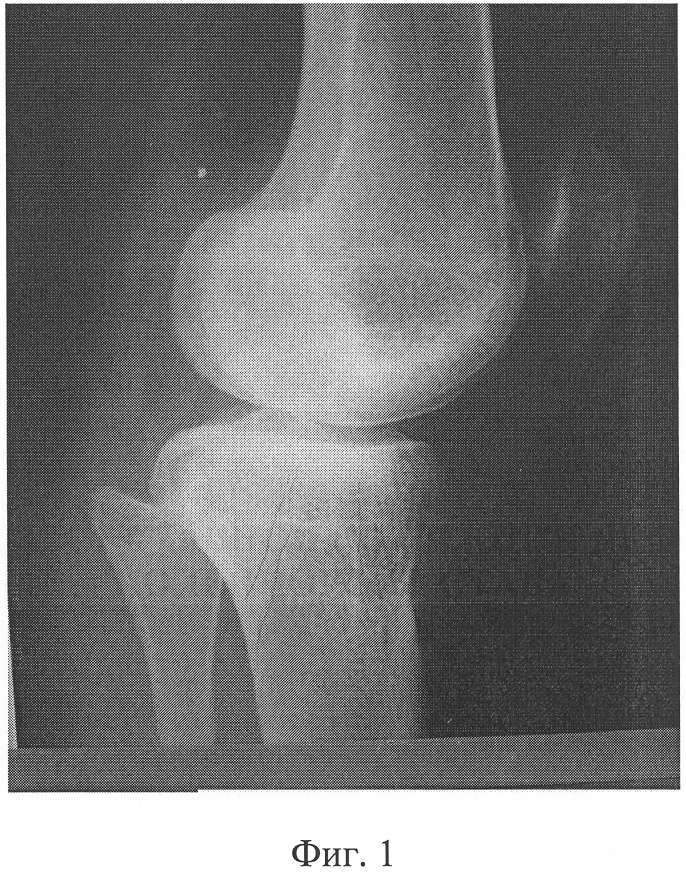

Фиг.3 – интраоперационная после остеотомий при фиксации костно-хрящевого фрагмента П-образно изогнутой спицей;

В СарНИИТО 13.12.05 было проведено оперативное вмешательство по запланированной схеме (фиг.5). Произвели дугообразный разрез по передневнутренней поверхности проксимального отдела левой голени длиной 12 см. В верхней трети левой большеберцовой кости выполнена корригирующая многоплоскостная остеотомия с формированием внесуставно костно-хрящевого суставного фрагмента. На задней поверхности голени вырезали клин углом в 10° и шириной 8 мм. Затем была пересечена в средней трети малоберцовая кость. Проведенными в сагиттальной плоскости П-образно изогнутой спицей Киршнера и стержнем костно-хрящевой фрагмент зафиксирован в аксиальной плоскости. Интраоперационно под рентгеноконтролем на голень наложен двухсекционный спице-стержневой аппарат внешней фиксации (фиг.4). Спица и стержень закреплены на верхней базовой опоре аппарата посредством тяговых устройств.